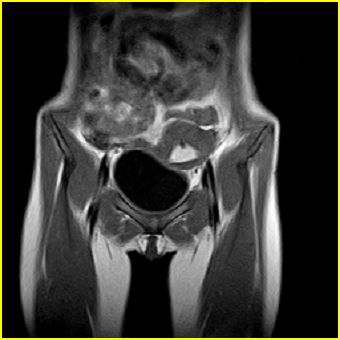

女、15岁、下腹疼痛2天,排尿困难1天。查体:处女膜闭锁,距处女膜约4至5cm处扪及一约5cm直径的圆形包块,张力较高,触痛明显、欠活动。b超提示子宫增大伴宫内增强回声团。

影像意见:子宫直肠陷凹积血。

更正影像意见:阴道积血。

处女膜闭锁,阴道积血

处女膜闭锁,阴道积血,子宫积血.

先天性处女膜闭锁,伴阴道积血,不除外先天性阴道粘液囊肿形成。

阴道积血,子宫积血.

子宫及阴道积血。

处女膜闭锁,伴子宫及阴道积血.